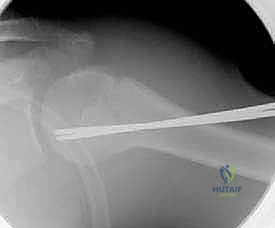

التثبيت بمسامير النخاع المرنة (TENs - Titanium Elastic Nails):

تُستخدم بكثرة في كسور الترقوة المعقدة للمراهقين أو كسور العضد. يتم إدخال مسمار مرن من التيتانيوم داخل التجويف النخاعي للعظم ليعمل كدعامة داخلية قوية تحافظ على استقامة العظم حتى يلتئم. -